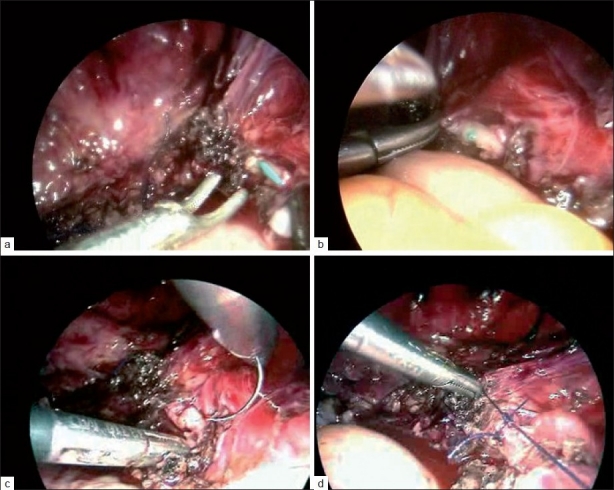

Objectives: To compare the risk of ureteric injury in total laparoscopic hysterectomy (TLH) using new vessel sealing devices (VSDs) and harmonic scalpel with simple scissors, bipolar and suturing. This was an evaluation of 1209 cases, carried out from May 1999 to April 2010.

Materials and methods: Out of 1209 patients, who had hysterectomies for various indications, TLH was done in 892 patients, 273 had vaginal hysterectomy and 44 had abdominal hysterectomy. We evaluated the incidence of ureteric injury in these cases.

Results: There was no mortality. In the group of vaginal and abdominal hysterectomy, there were no ureteric injuries. In the TLH group, we had 390 cases with simple scissors, bipolar and suturing with no ureteric injury. In 502 cases, new VSDs, e.g., plasma kinetic gyrus, Martin Maxim with Robi grasper, with or without harmonic 5 mm scalpel/ace were used. There were five ureteric injuries, all on the right side (one double ureter): first case was with Martin Maxim and Robi grasper, two with plasma kinetic gyrus 10 mm trissector, one with harmonic scalpel and the last one with scissors. We evaluated the reasons for such ureteric injuries, with experienced laparoscopic surgeons and the best possible set up. There were seven conversions to open surgery out of 892 cases of TLH, more due to poor case selection.